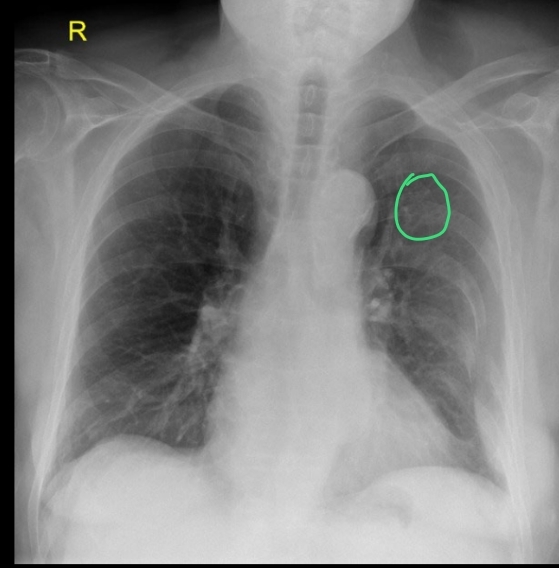

Qué se ve en una Rx de un hemotórax

• Derrame pleural

• Borammiento de la silueta cardíaca